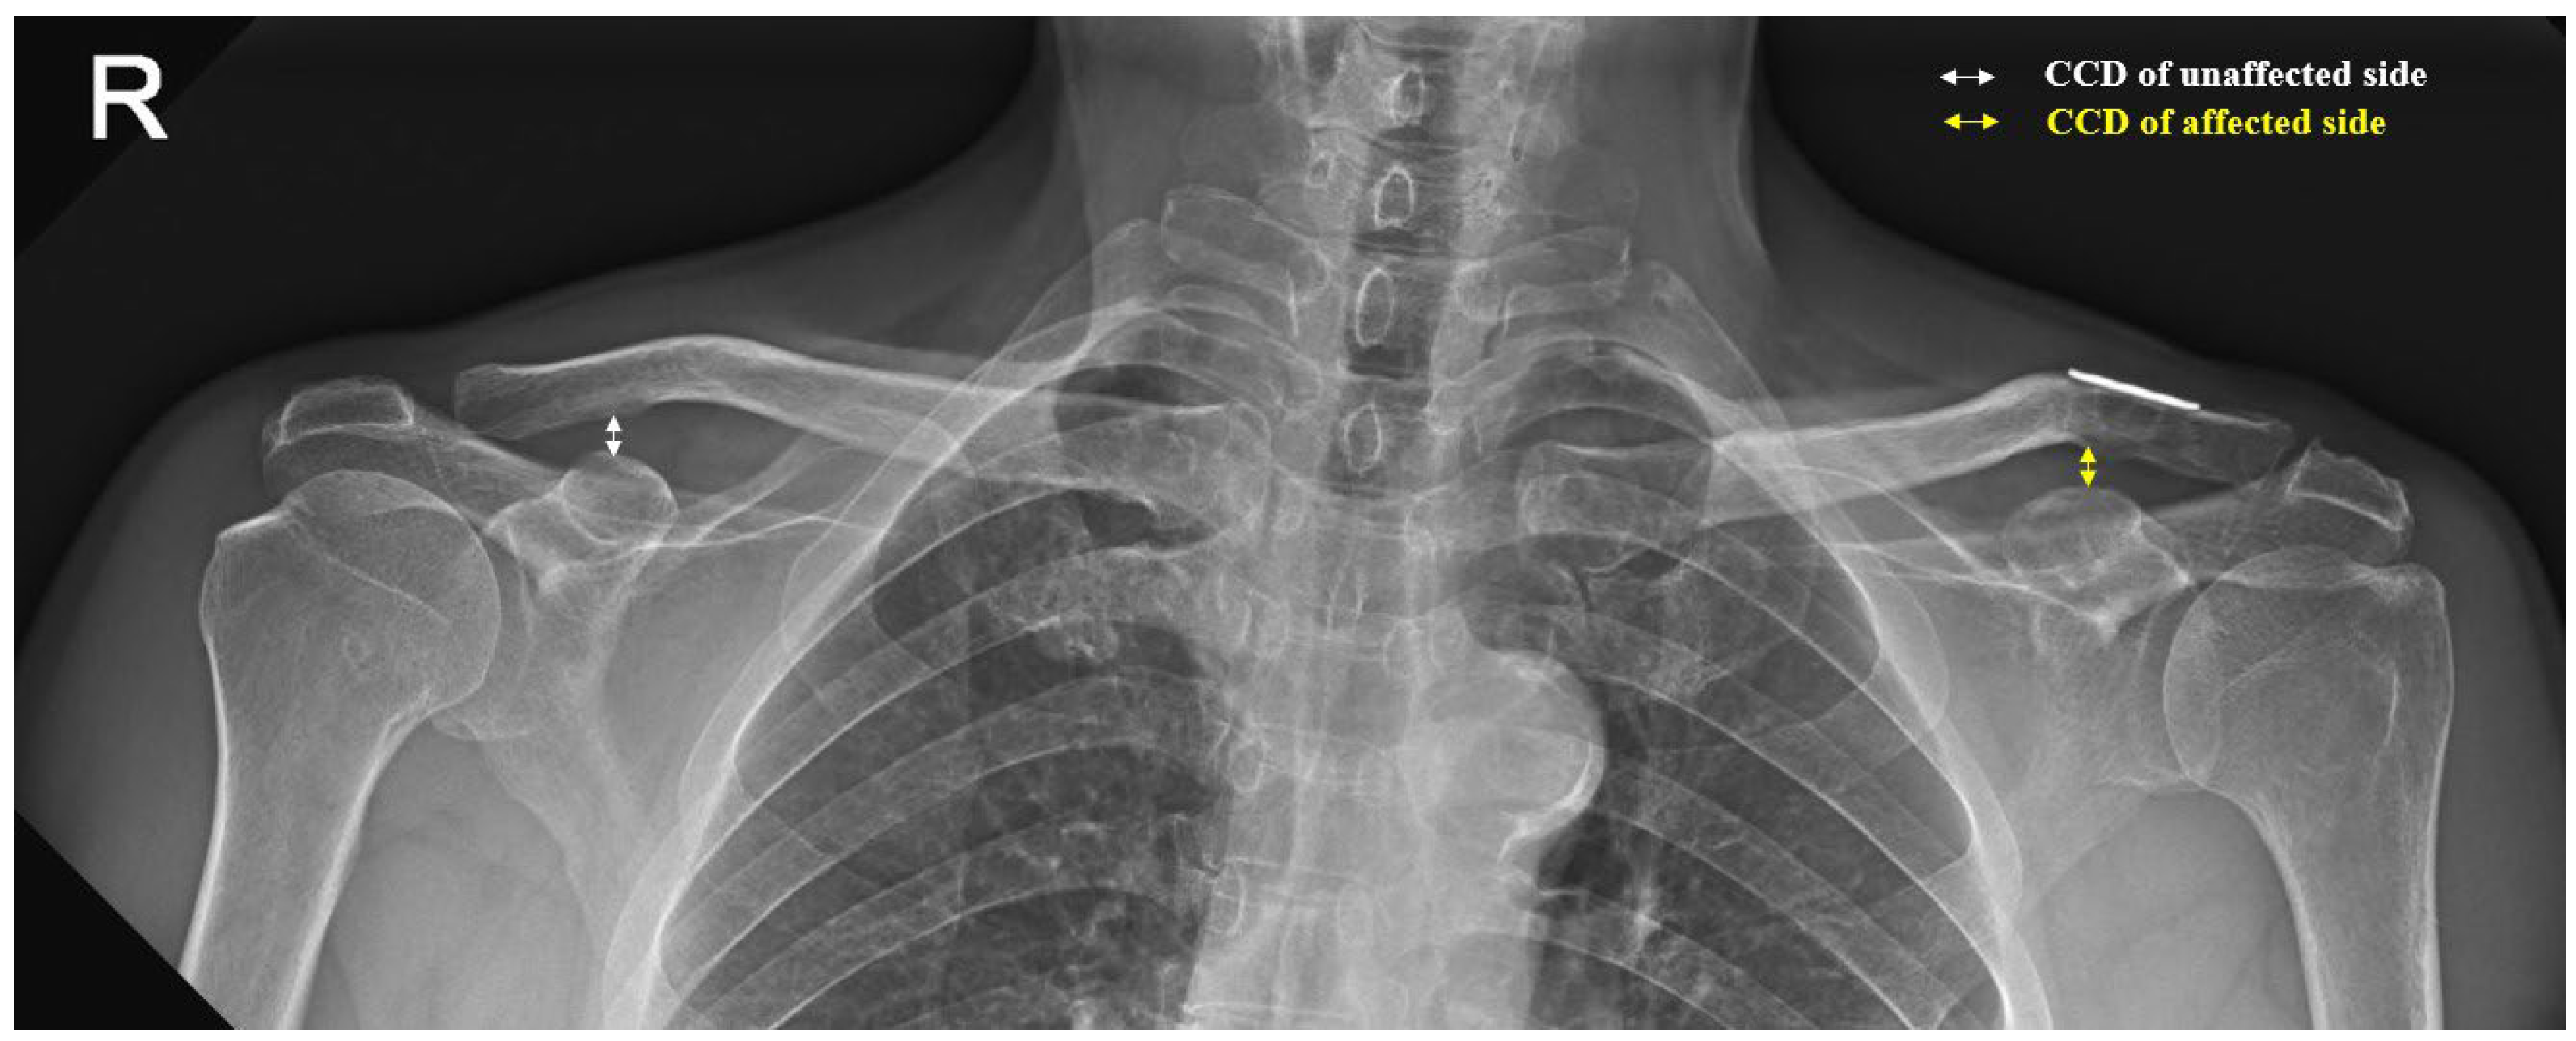

The AP images of both clavicles were used for measuring the CCD, which was defined as the shortest distance between the uppermost level of the coracoid process and the lowest level of the clavicle in millimeters. We assessed changes in the reductions using the CCD ratios between the affected and unaffected sides (Figure 3). We classified the reductions as adequate reduction or loss of reduction based on the CCD ratio. An adequate reduction was defined as a CCD ratio ≤ 1.1 and loss of reduction was defined as a CCD ratio > 1.1. The other radiological outcomes recorded were postoperative clavicular fracture, AC joint arthritis, distal clavicular osteolysis, and CC ossification.

Figure 3.

A 24-month postoperative AP radiograph of both clavicles showing the coracoclavicular distance (CCD), defined as the shortest distance between the uppermost level of the coracoid process and the lowest level of the clavicle. The CCD ratio was defined as the CCD of the affected (yellow line) and unaffected (white line) clavicles. In this case, the CCD ratio is CCDaffected/CCDunaffected = 1.01.